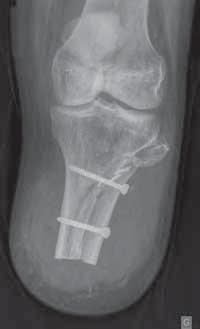

1.Wskazaniaurazowe

dalszej podudzia